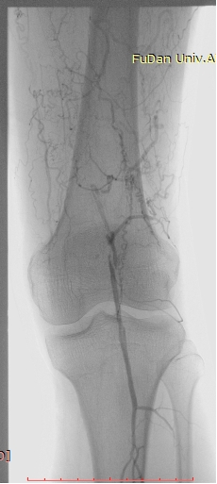

病例-1 男性,77岁,左下肢SFA支架术后7年,旁路术后3年静息痛 ABI:左侧 0.35